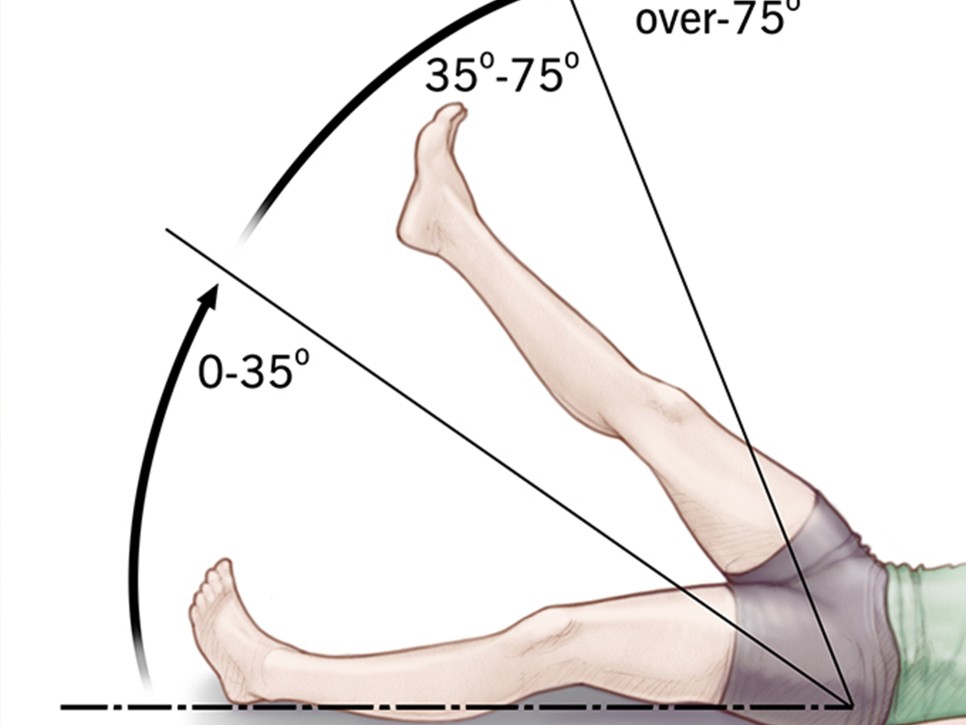

침대에 누워 증상인 얼다리를 쭉 뻗어 올릴 때 30~70도 사이에 허벅지나 종아리 뒤쪽 통증이 있는 것으로 의심할 수 있습니다. 단, 단순 요통 환자 분도 비슷한 증상을 보일 수 있습니다. 진단을 하기 위해서는 ct, MRI 촬영 등이 필요하게 될 수 있습니다.